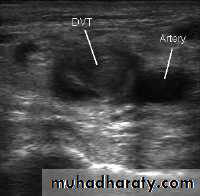

Doppler ultrasonography

Duplex US with color-flow imaging (sometimes called triplex ultrasound):This is a special type of 2-dimensional ultrasound that uses Doppler-flow information to add color for blood flow in the image. Vessels in the blood are colored red for flow in one direction and blue for flow in the other, with a graduated color scale to reflect the speed of the flow.

Duplex ultrasonography , due to its high sensitivity , specificity and reproducibility , has replaced venography as the most widely used test in the evaluation of DVT.